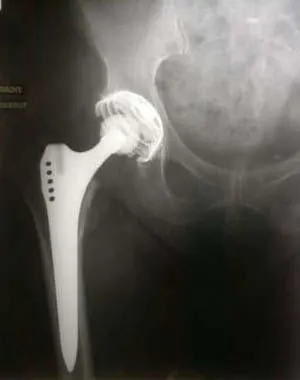

J’ai une prothèse de hanche

La prothèse de hanche permet de faire du sport pratiquement normalement. L’usure des implants devrait en théorie être accélérée, mais cela n’est pas évident. Le conseil prodigué en général est de faire ce qu’il plaît ; c’est d’une part la raison pour laquelle l’indication opératoire a été portée, d’autre part l’entretien de la trophicité musculaire et articulaire ne peut être que bénéfique.

La limite que l’on peut avancer concerne le risque de luxation. Selon le type d’intervention, la luxation survient en flexion de hanche et rotation interne du membre inférieur, ou en extension - rotation externe. Cela doit être précisé par le chirurgien.